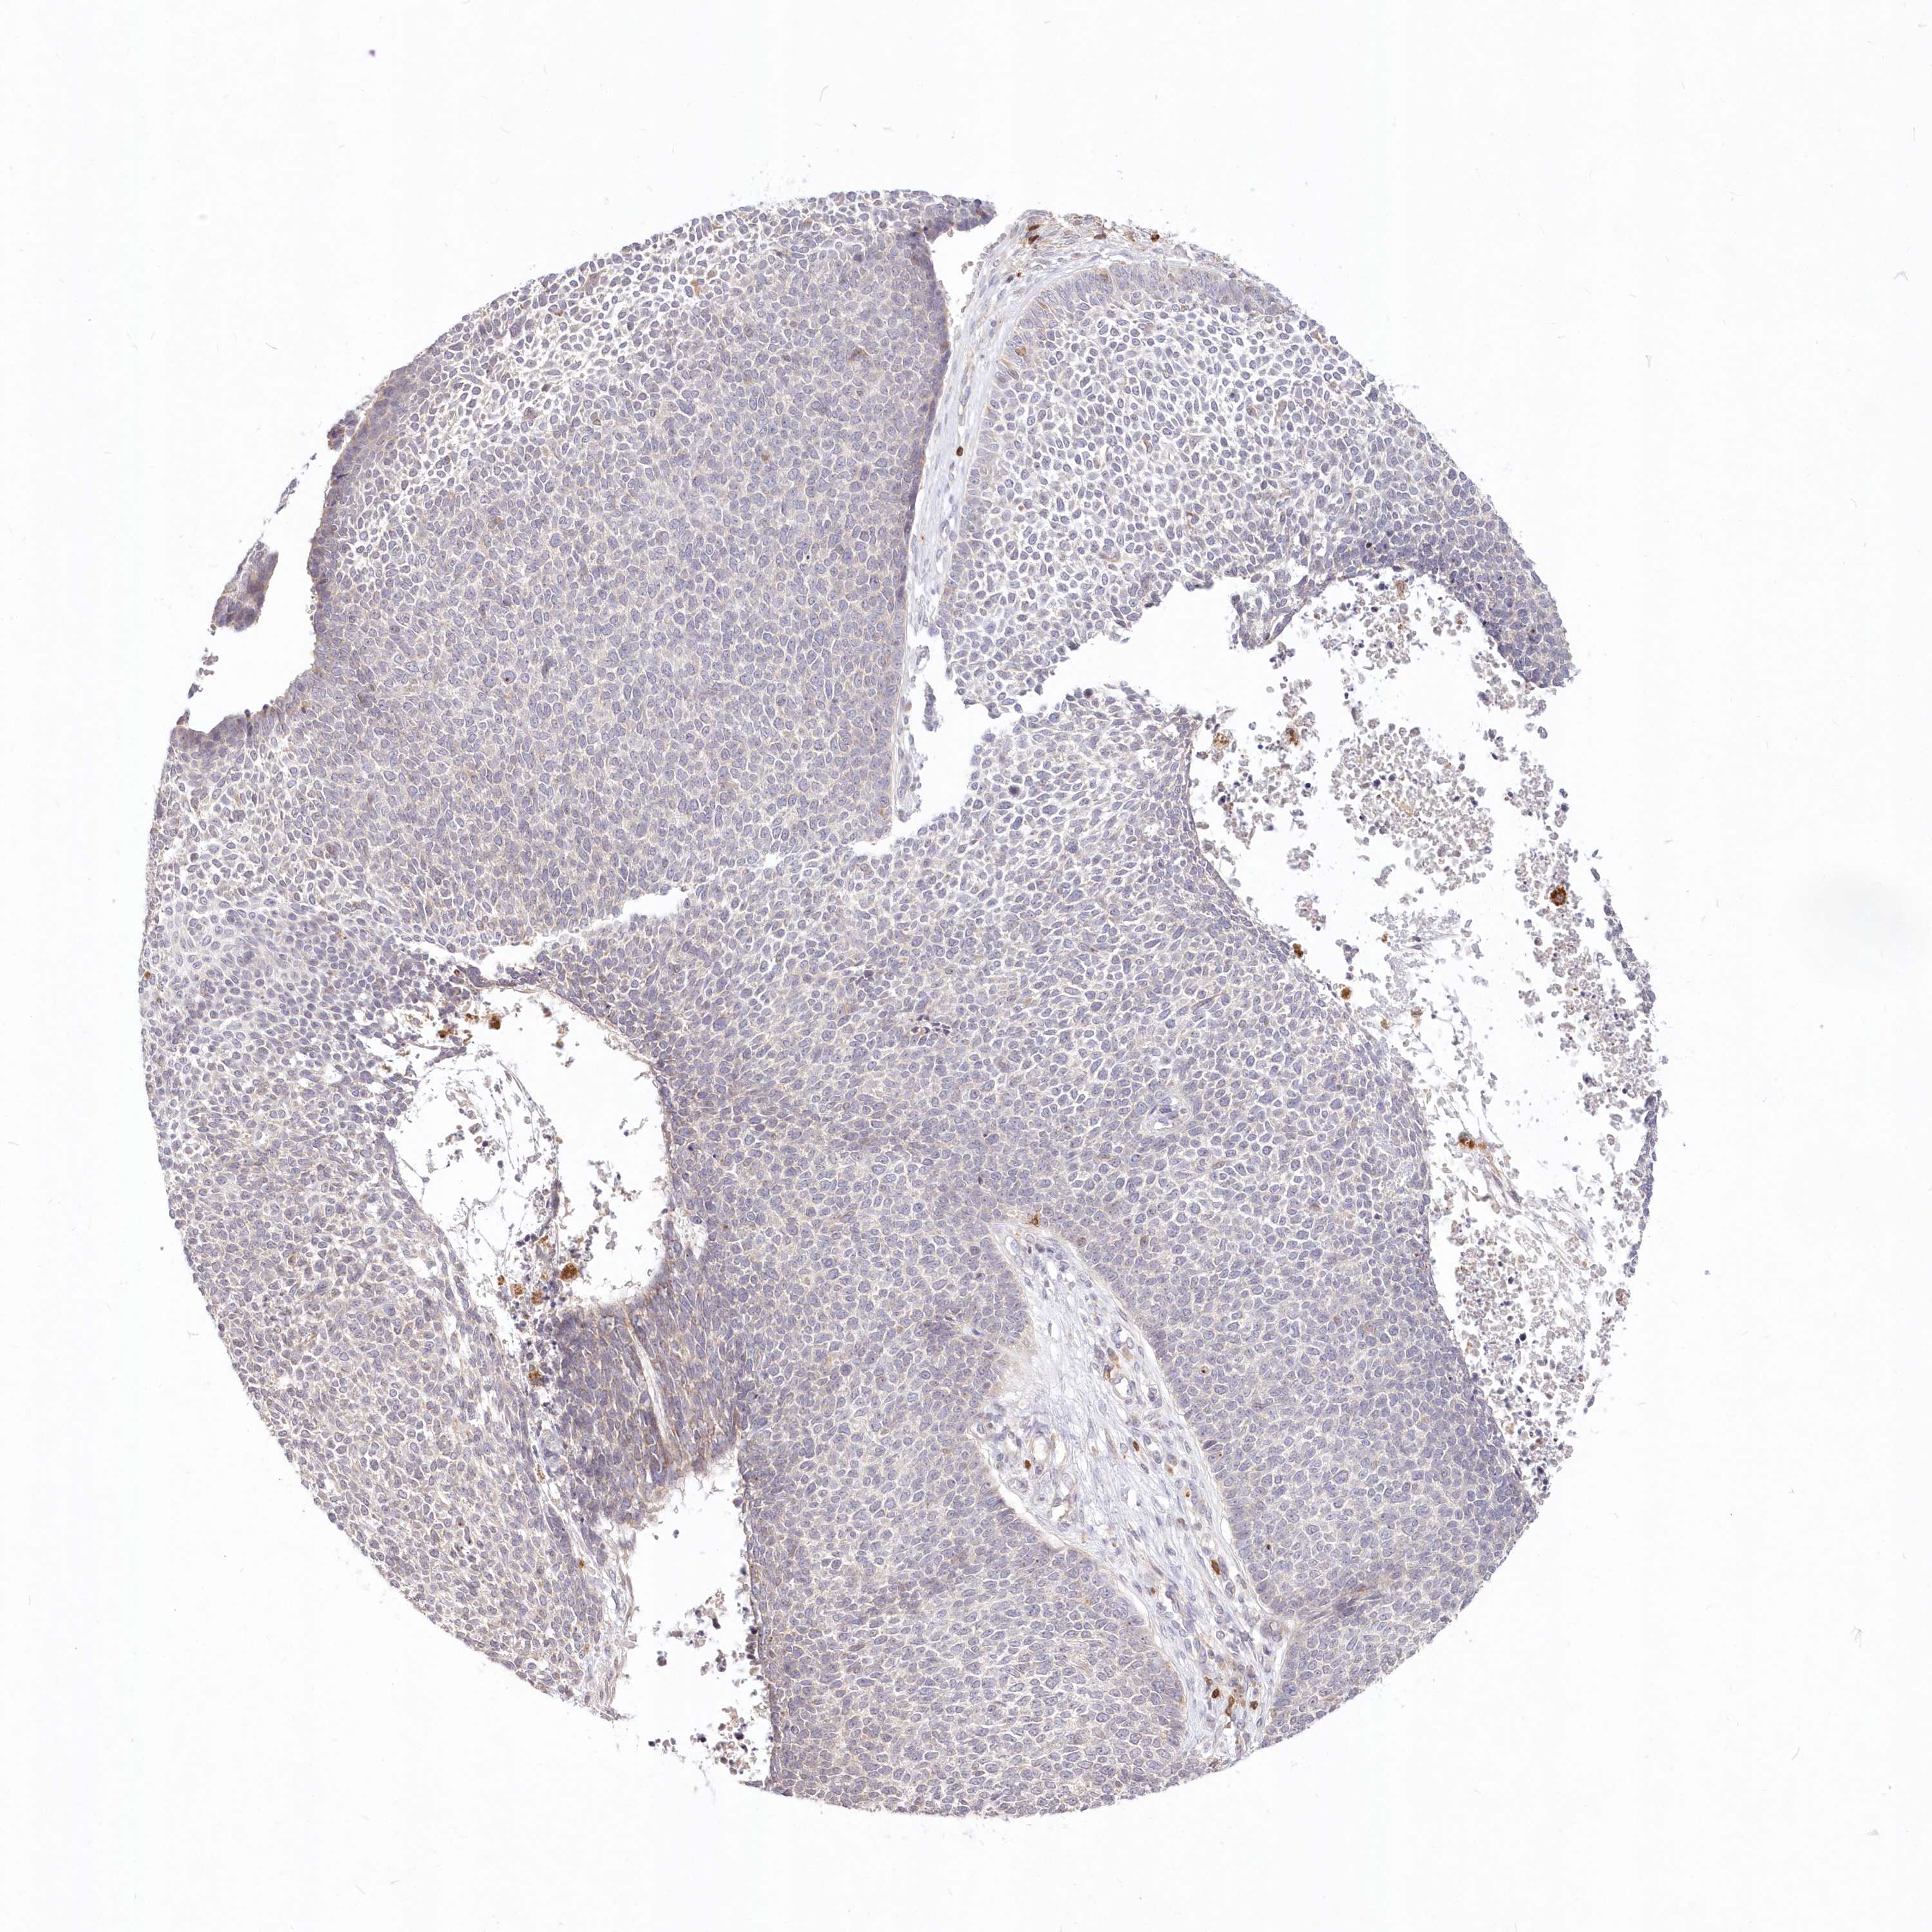

Basal cell and squamous cell cancer

SKIN CANCER - Protein expressioni

A mouse-over function shows sample information and annotation data. Click on an image to view it in a full screen mode. Samples can be filtered based on level of antibody staining by selecting one or several of the following categories: high, medium, low and not detected. The assay and annotation is described here.

Each image is clickable and will lead to virtual microscopy that enables deeper exploration of all samples and also displays staining intensity scores, fraction scores and subcellular localization as well as patient and tissue information for each sample.

Antibody HPA034516

Squamous cell carcinoma, NOS

Squamous cell carcinoma, metastatic, NOS